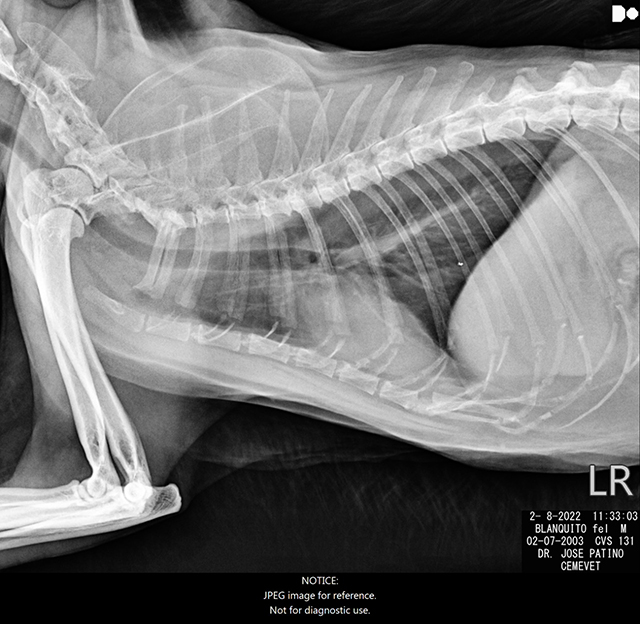

Pero ahora, nuestro peludo mayor ha desarrollado dos tumores horribles, y uno de ellos está creciendo muy agresivamente en su espalda (como se puede ver en las fotos) por lo que necesita ser removido lo antes posible para evitar que invada sus órganos internos o su columna. Mientras tanto, vive muy incómodo y con mucho malestar. Hasta el punto, que recientemente nos hemos visto obligadas a cubrir el bulto con una venda para que no se haga daño cuando se baña ansiosamente tratando de quitarse el tumor que tanto le molesta.

But now, our oldest furry boy has developed two awful tumors. One of them is very aggressively growing on his back (as you ca see on the pictures) and it needs to be removed as soon as possible before it invades his internal organs. Meanwhile, he is now in great discomfort and we’ve been forced to cover the lump so he won’t hurt himself while bathing.

ES. Finalmente hemos logrado que se haga la cirugía para extirpar el tumor más grande. Luego de ser removido todos quedamos muy sorprendidos por el tamaño y peso del tumor (120gr) que era bastante grande y pesado en relación con el tamaño y peso de Blanco. Le han tomado 12 puntos, tiene una herida inmensa que está sanando como se esperaba, a pesar que ha tenido un par de complicaciones.

EN. We have finally managed to get Blanco’s surgery done and the largest tumor has been finally removed. After the surgery we were all very surprised by the size and weight of the tumor (120gr) which was quite large and heavy in relation to Blanco’s size and weight. 12 stitches were taken, he has a huge wound that is thankfully healing as expected, even though he’s had a couple complications.

Los médicos veterinarios coinciden en que debemos esperar algunas semanas para poder revaluar el segundo tumor que tiene en el lomo. Es bastante probable que este tumor sea posvacunal, algo que nos preocupa mucho porque estos tumores suelen ser muy persistentes y peligrosos. Pero por la edad, nos vemos obligadas a esperar antes de reconsiderar las posibilidades de otra cirugía.

Doctors agree that we must wait a few weeks to be able to reevaluate the second tumor on his back because It’s very likely a post-vaccinal tumor. This very worrying because these kind of tumors tend to be very persistent and aggressive. But due to his age, we are forced to wait some time before reconsidering the possibility of another surgery.